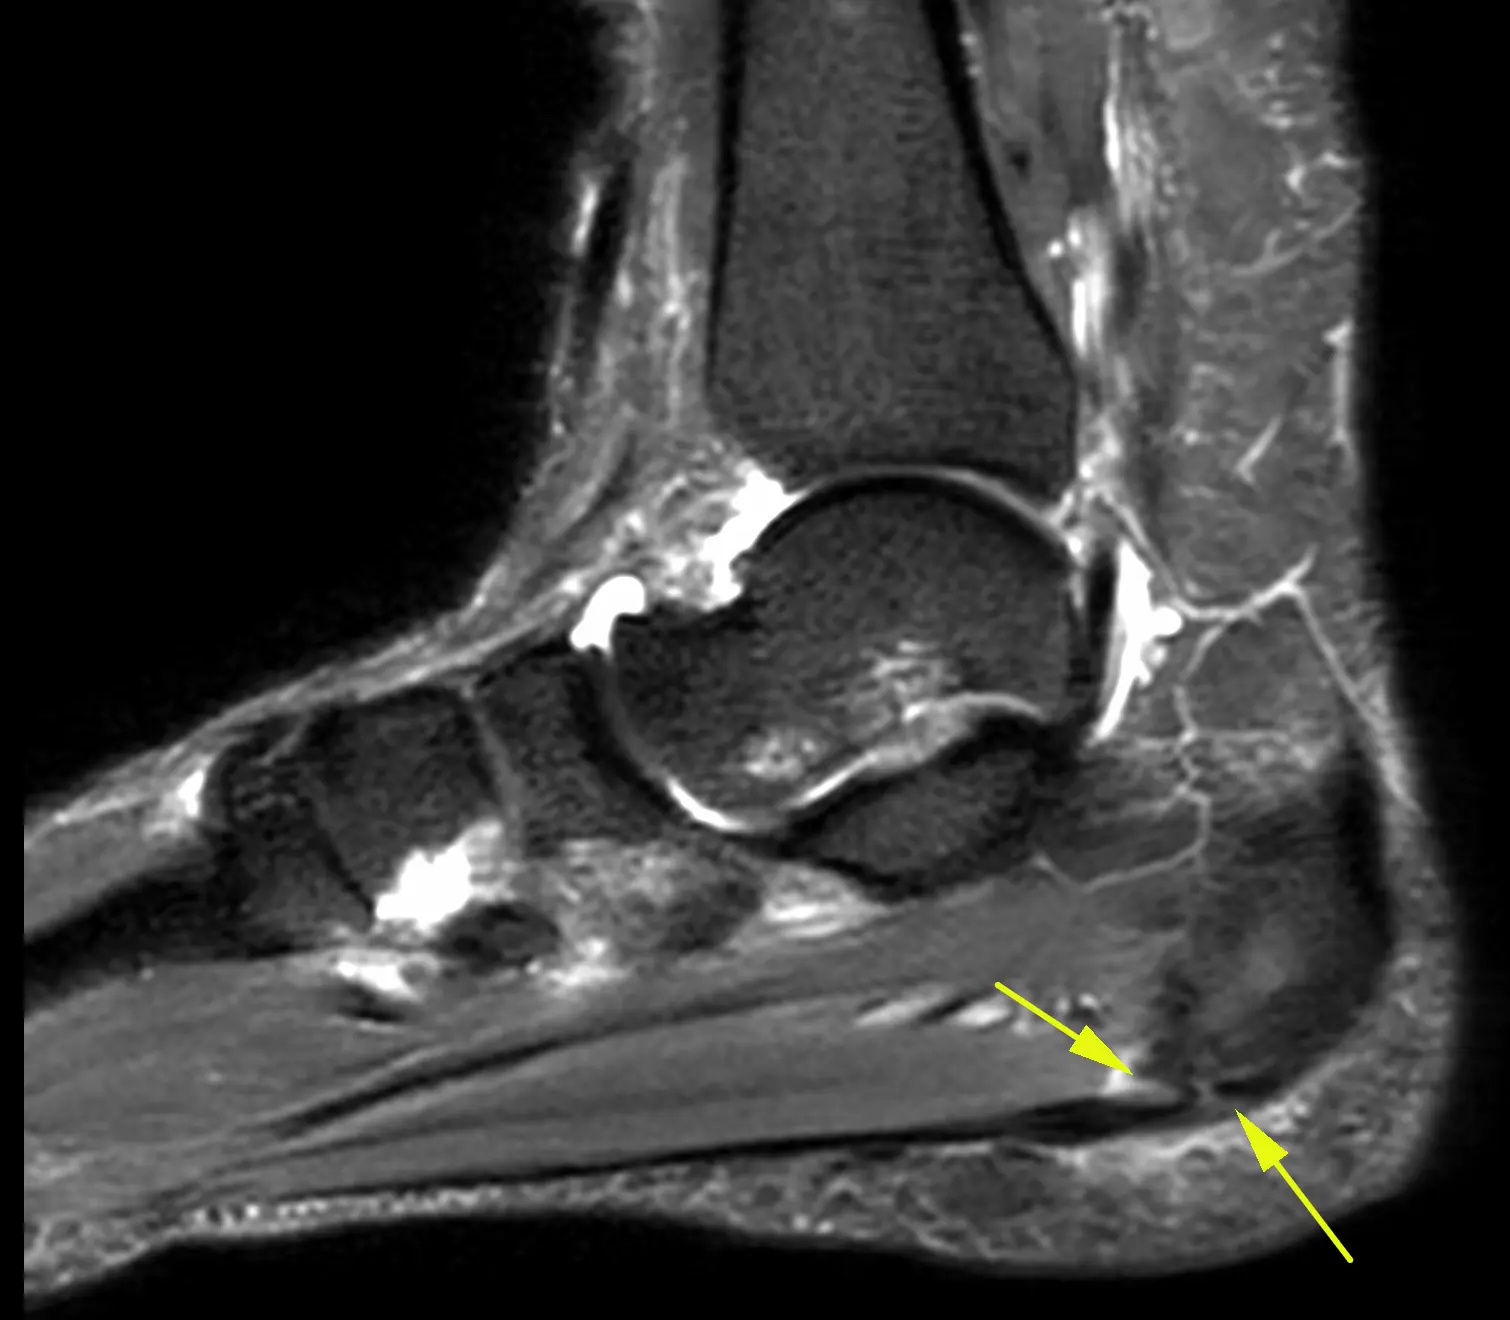

Один из вариантов тарзальной коалиции: таранно-пяточный синдесмоз. Напомню, что тарзальной называется патологическое сочленение между костями плюсны и предплюсны, может быть в виде синостоза, синхондроза и синдесмоза. Если имеется синдесмоз (как здесь), то хроническая его перегрузка приводит к артрозу и всем его типичным проявлениям, как здесь: неровностям контактных поверхностпей, субхондральные отёк и полости (кисты). Локально болит, особенно при нагрузке. Пациент 26 лет.